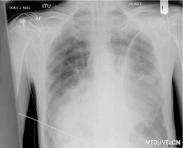

張力性氣胸

• 張力性氣胸

628健康網(wǎng)為您分享有關(guān)張力性氣胸的癥狀,張力性氣胸的治療方法,張力性氣胸的預(yù)防知識,張力性氣胸的癥狀圖片,張力性氣胸...